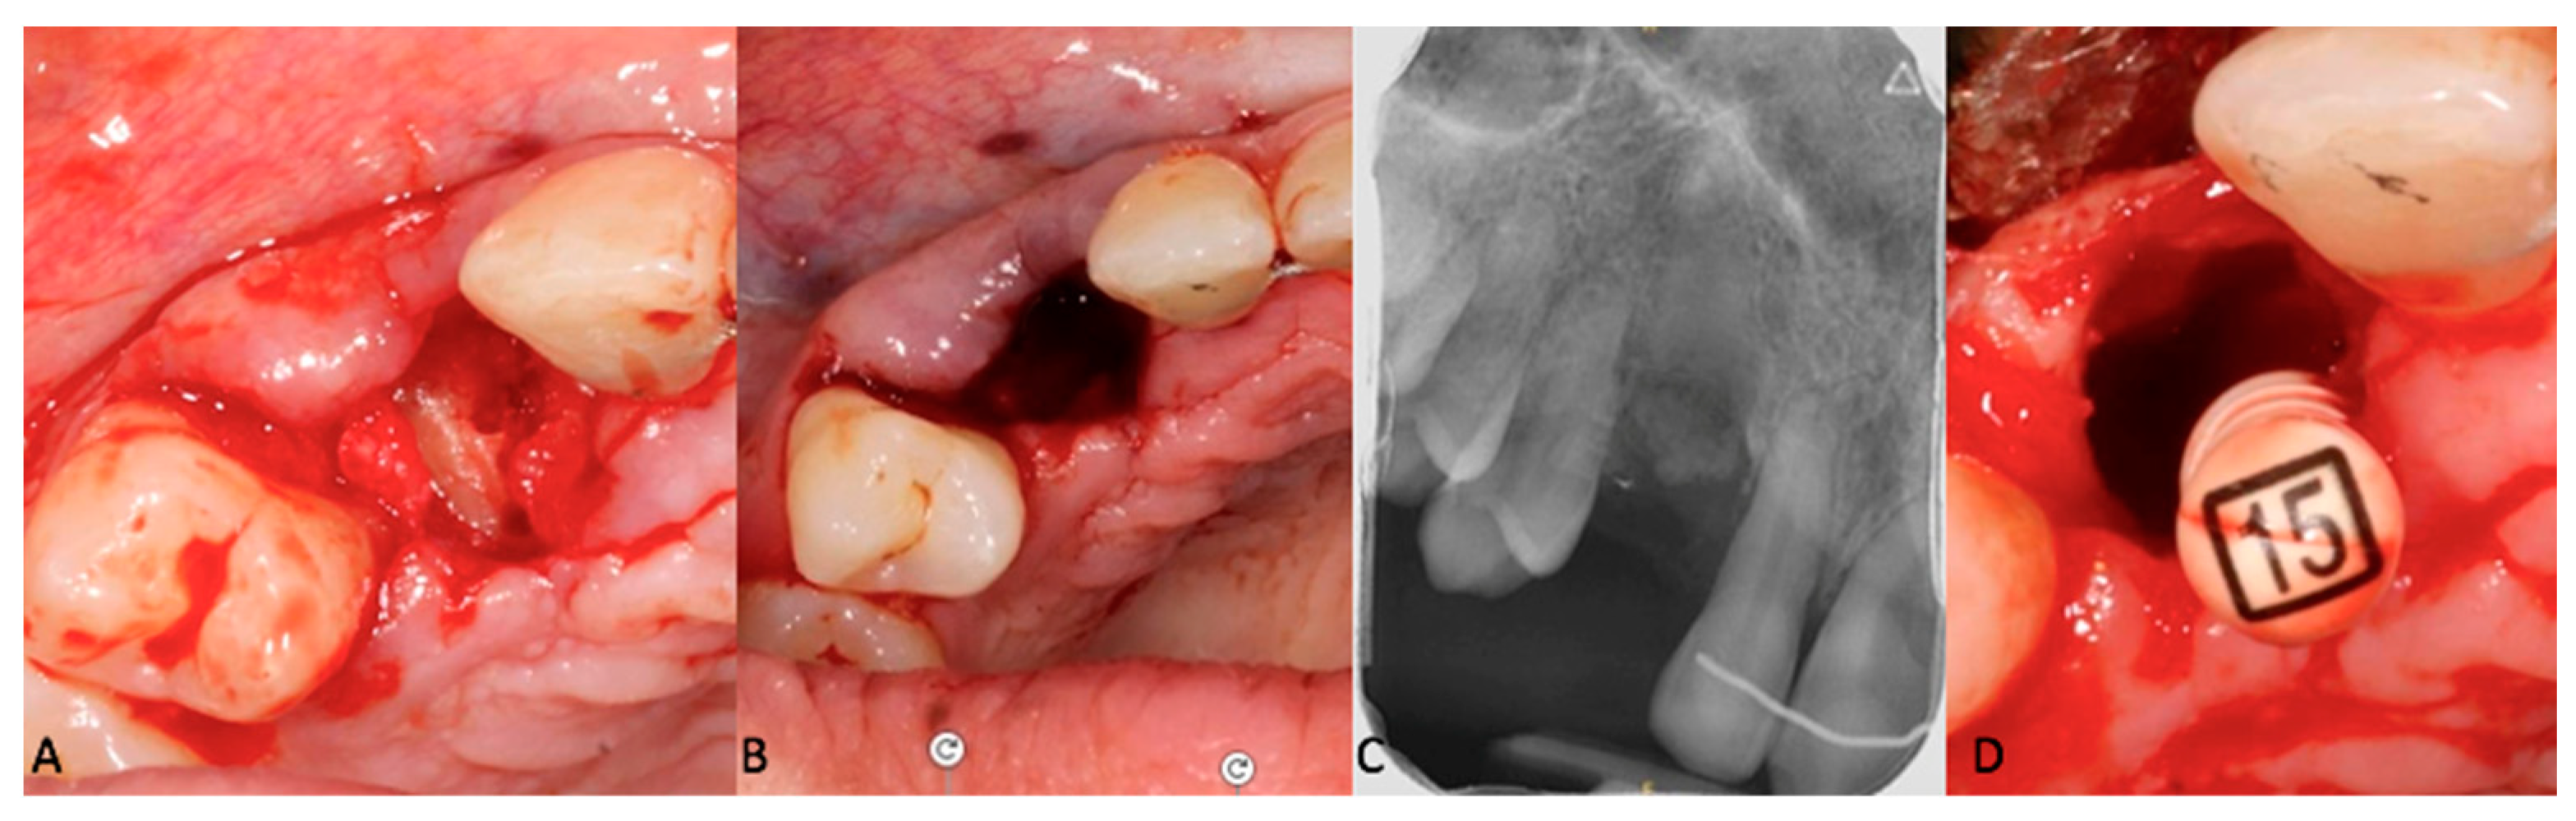

Figure 6. (AC): Pre-operative view of the decoronation. (C): Post-operative intraoral teleradiograph. (D): Pre-operative view of the supra-radicular blood clot formation induced by the remaining pulp parenchyma from the apical fragment.

The next step involved the decoronation of tooth # 13 while aiming to preserve the alveolar ridge. Due to the thin buccal cortical plate (<1 mm) (Figure 2), as well as the position and size of the canine, a full tooth extraction posed a risk of bone damage and could have resulted in an unpleasant gingival defect. To avoid such complications, after removal of the buccal flap, the crown of tooth # 13 was vertically divided into two parts using an orange contra-angle and fissure bur (H162SL.314.014 VPE 1 tungsten bur, Komet, Dublin, Ireland). Both fragments were then extracted, and the remaining root was progressively milled with a handpiece bone ball bur (H141.104.027 VPE 1 tungsten bur, Komet, Dublin, Ireland), while extensive irrigation and optical aids (Orascoptic loupes, Madison, WI, USA) were used to remove all residual enamel. Intra-operative radiographic controls were used to monitor the progress of the decoronation and assess the size of the residual root. An endodontic file (K file, size 15) was used to remove the remaining pulp parenchyma from the apical fragment, inducing intracanal bleeding and promoting supra-radicular blood clot formation (Figure 6). Sutures (5–0, Vicryl Rapide, Raritan, NJ, USA) were applied and the buccal margin was brought closer to the palatal margin to avoid scarring in the aesthetic zone.